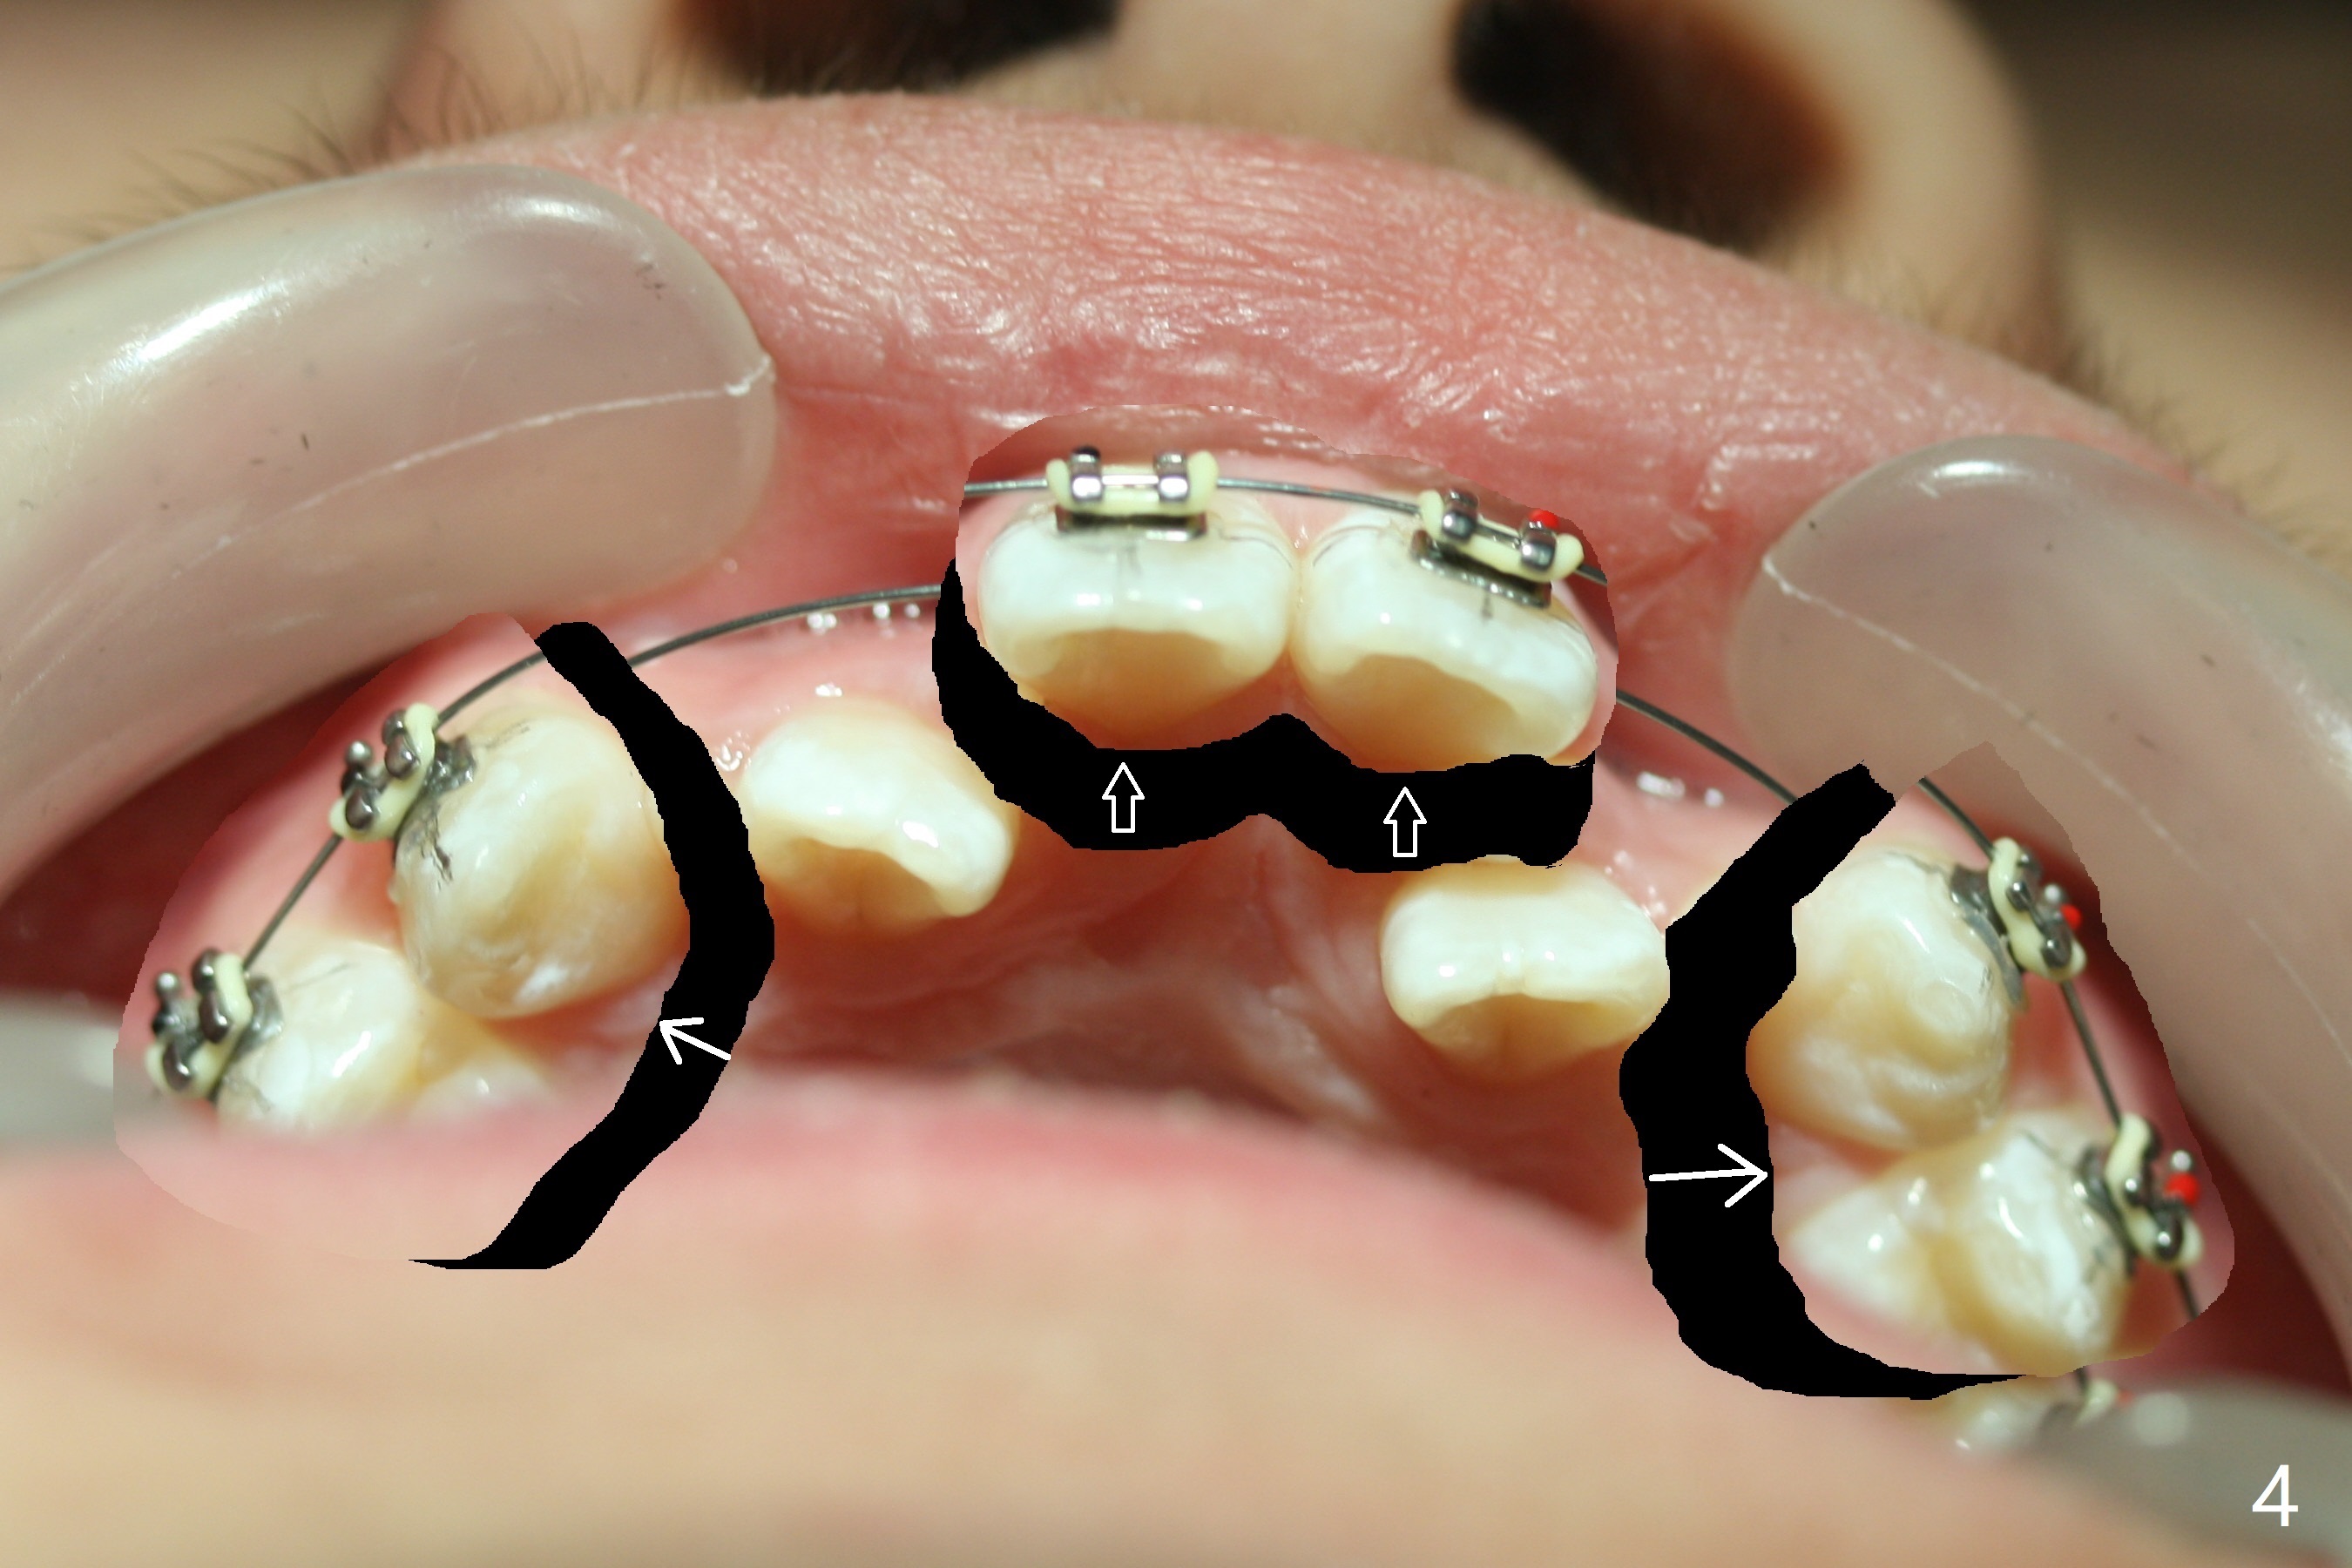

Cephalometric analysis shows Class III skeletal relationship. The roots of the upper anterior teeth (Fig.1,3 *) are prominent before treatment. In order to correct the cross bite of U2s (Fig.2,5), the upper arch needs expansion (Fig.4). Will the arch expansion cause buccal plate loss of the upper teeth? The upper dental midline matches the lower one by using the left open coil spring only (4 months 10 days post banding, Fig.6).